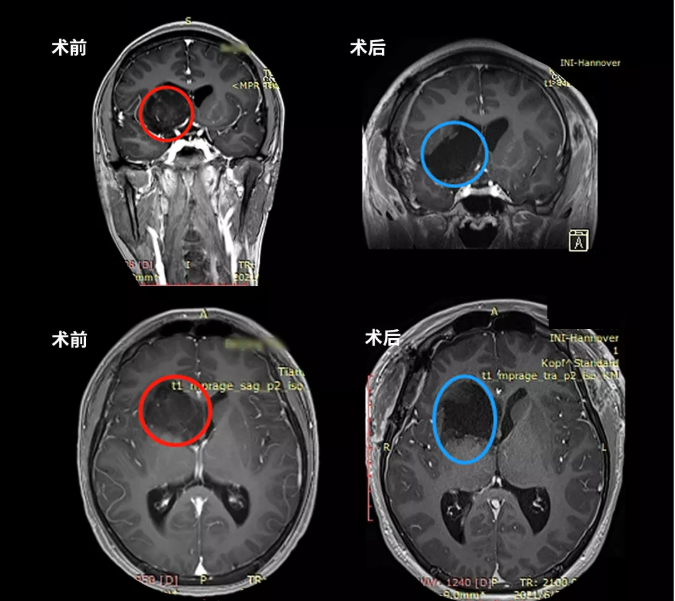

术前术后MR磁共振对比,术前丘脑较大占位,压迫岛叶及脑室,脑室增大。术后MR提示肿瘤近全切,占位效应解除,无新发脑损伤等。